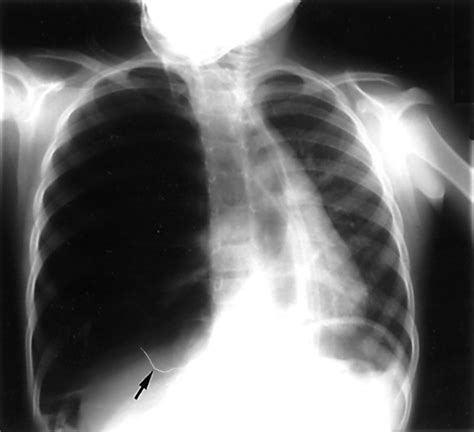

Traumatic Pneumothorax

Traumatic pneumothorax results from chest trauma, such as a rib fracture or penetrating injury. On an X-ray, it may be associated with other injuries, such as rib fractures or hemothorax (blood in the pleural space).

6. Look for Associated Findings: Identify any additional findings, such as rib fractures, bullae, or hemothorax, which may provide clues about the underlying cause.